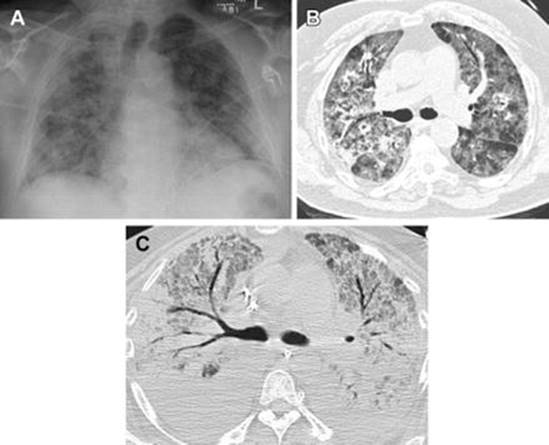

In patients with ARDS , chest radiographs reveal bilateral opacities not attributable to effusions, pneumothorax or lung nodules, and pulmonary edema not explained by fluid overload or cardiac failure (Fig. 15.1) [36]. In patients with ARDS, the ratio of arterial partial pressure of oxygen to fraction of inspired oxygen (PaO2/FiO2) is expected to be less than 300 mmHg; this ratio will be lower in more severe disease [36].

Fig. 15.1

Acute respiratory distress syndrome (ARDS). (a) AP chest radiograph shows low lung volumes and diffuse bilateral pulmonary opacities. (b) Axial CT image in the same patient shows ground-glass and consolidative opacities without pleural effusions. (c) Axial CT image from another patient shows dense bilateral consolidation with air bronchograms and diffuse ground-glass opacity (Reprinted from Bentz and Primack [11], with permission from Elsevier)